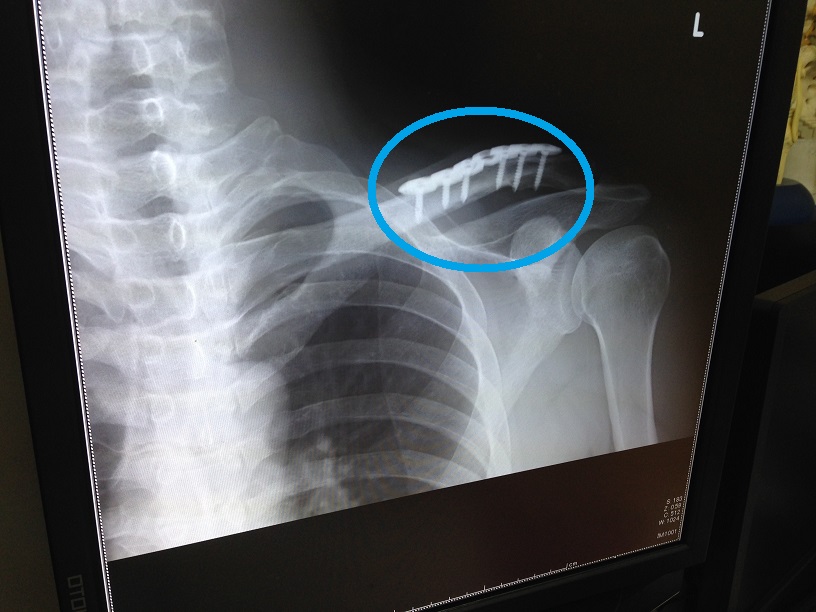

手術怖い

取り出したものは学校に寄贈(廃棄?)予定です。

関心ある人は事務室まで